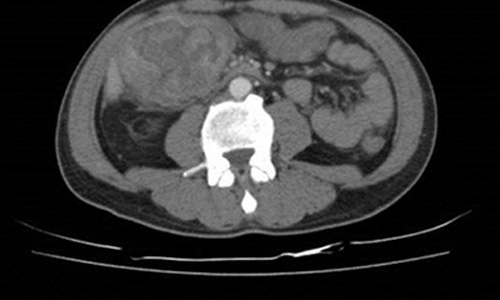

臺北市立聯合醫院仁愛院區血液腫瘤科林哲斌醫師解釋,假設將大腸由脾臟彎處區分成左、右大腸,升結腸屬右大腸,其中的糞便尚未成型,所以在此處形成的大腸腫瘤不易早期發現,較常像林先生的狀況,等到貧血了才被發現,腫瘤也長大到7.4公分。